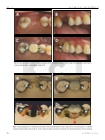

Purpose: The object of this clinical study was to evaluate the short-term outcome of modified resin-bonded fixed partial dentures which utilizes the original tooth undercuts and different path of insertion of components.

Materials and methods: 71 units of modified RBFPDs that were used in 21 patients at the Department of Prosthodontics, College of Dentistry, Yonsei University were evaluated. The follow-up period was up to 25 months, the mean being 7 months. Survival rate, mobility, percussion, probing depth, bleeding on probing, plaque index was recorded and radiographs were taken to monitor alveolar bone loss.

Results & Conclusion: Within the limits of this short term retrospective study, it was concluded that: 1. No mechanical failure such as debonding or fracture of the framework was found during the follow-up period. 2. The periodontal apparatus was stable and no clinical change was observed after prosthetic treatment. 3. No significant marginal bone loss was found in the radiographic evaluation.기사명 | 저자명 | 페이지 | 원문 | 목차 |